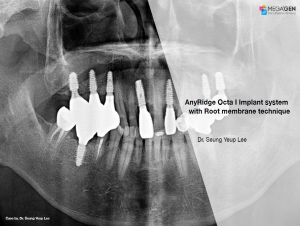

Dr. Achraf Souayah,Edentulous,Aesthetic zone,Maxillary Anterior,Maxillary Posterior,Mandibular Anterior,Mandibular Posterior,Guided surgery,Sinus Elevation,Immediate Placement,AnyRidge,Overdenture system,Meg-Rhein,MILA Kit,Clinical case